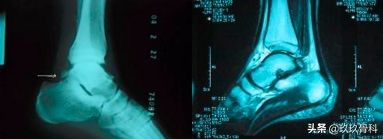

跟腱陈旧断裂

跟腱腱病

跟腱断裂▲▲▲

病因:直接外力、开放伤、闭合伤、间接外伤

病理:26/38例伤前有跟腱腱围炎病史

病理改变:主要为跟腱的坏死、纤维变、纤维截断及腱周围组织血管增生、血管内膜增厚。

术中所见:断端呈马尾状,间隙有血肿,但出血少,腱围同时破裂,跖肌腱常完好。

损伤机制:在踝背伸60-70度位突然用力蹬地或踏跳